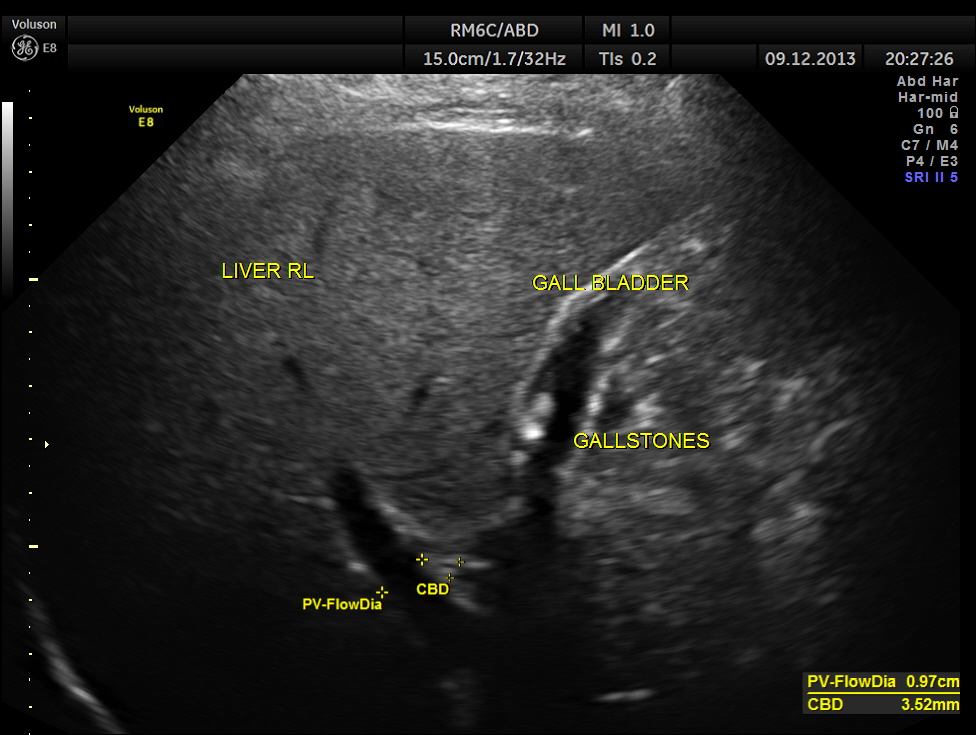

This was a 55-year-old gentleman who was being evaluated for painless hematuria.

He had incidental gallstones.

Usually the patient and the surgeon are interested in knowing the number of gallstones . I always have felt that the number would not matter . But is there a difference between 2D , 3D and more advanced high-definition rendering ? Please decide for yourself.